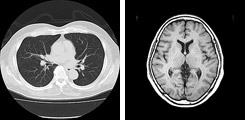

放射線部

当院は県内の総合病院の中でも早くからフィルムレス化を行い、システム及び業務の効率化を進めると共に急性期病院として、 診療放射線技師は24時間体制で救急時の放射線検査に対応しています。